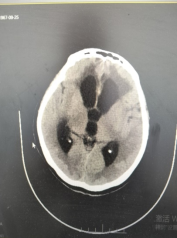

术前影像:CT提示明显交通性脑积水,脑室系统扩大。